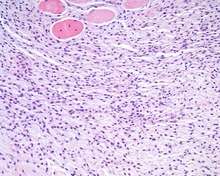

An intermediate power hematoxylin and eosin stained section of an ectomesenchymal chondromyxoid tumor, showing skeletal muscle entrapment. Note the "net-like" appearance (lower portion).[5][6]

The overlying surface epithelium is intact and unconnected to the well circumscribed, but unencapsulated ectomesenchymal chondromyxoid tumor of the tongue. There are numerous skeletal muscle bundles at the periphery of the tumor. - The tumor is made up of small round, oval, spindle, or stellate cells that have a very monotonous appearance. There are small dark nuclei with variably amounts of light to basophilic cytoplasm.[1][5][7]